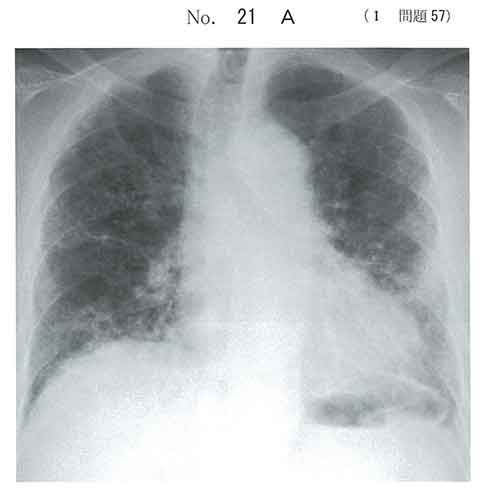

画像所見:肺高分解能CT撮影で、地図状のスリガラス様陰影を呈する。

honeycomb lungとfine cracklesだけでaにしました。何も考えない方が得する問題。

○a 間質性肺炎(IPF疑い).

肺胞蛋白症にしてはやや高齢だと思います。高齢重喫煙者の両側下肺のfine crackleであれば最も考えやすいのはIPFではないでしょうか。